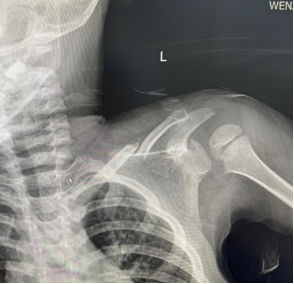

朱某,男,2016-3-15出生,因“跌倒致左肩疼痛伴活動受限2小時”2019年12月12日來我院門診。檢查發現左鎖骨區見腫脹、畸形,明顯壓痛,左肩活動受限。本院X線攝片示:左鎖骨骨折,斷端明顯重疊移位(圖1),予以8字繃帶外固定制動,定期隨訪。2020年1月17日復診述左肩無腫痛,活動基本正常,攝片示:左鎖骨骨折,斷端對線欠佳,局部明顯骨痂形成(圖2)。2020年6月8日再次復查攝片示:左鎖骨骨折,斷端對線可,已骨性愈合(圖3)。2023年9月26日再復查攝片示:左鎖骨骨折部位已完成塑形,與健側無明顯差異(圖4)。

圖1